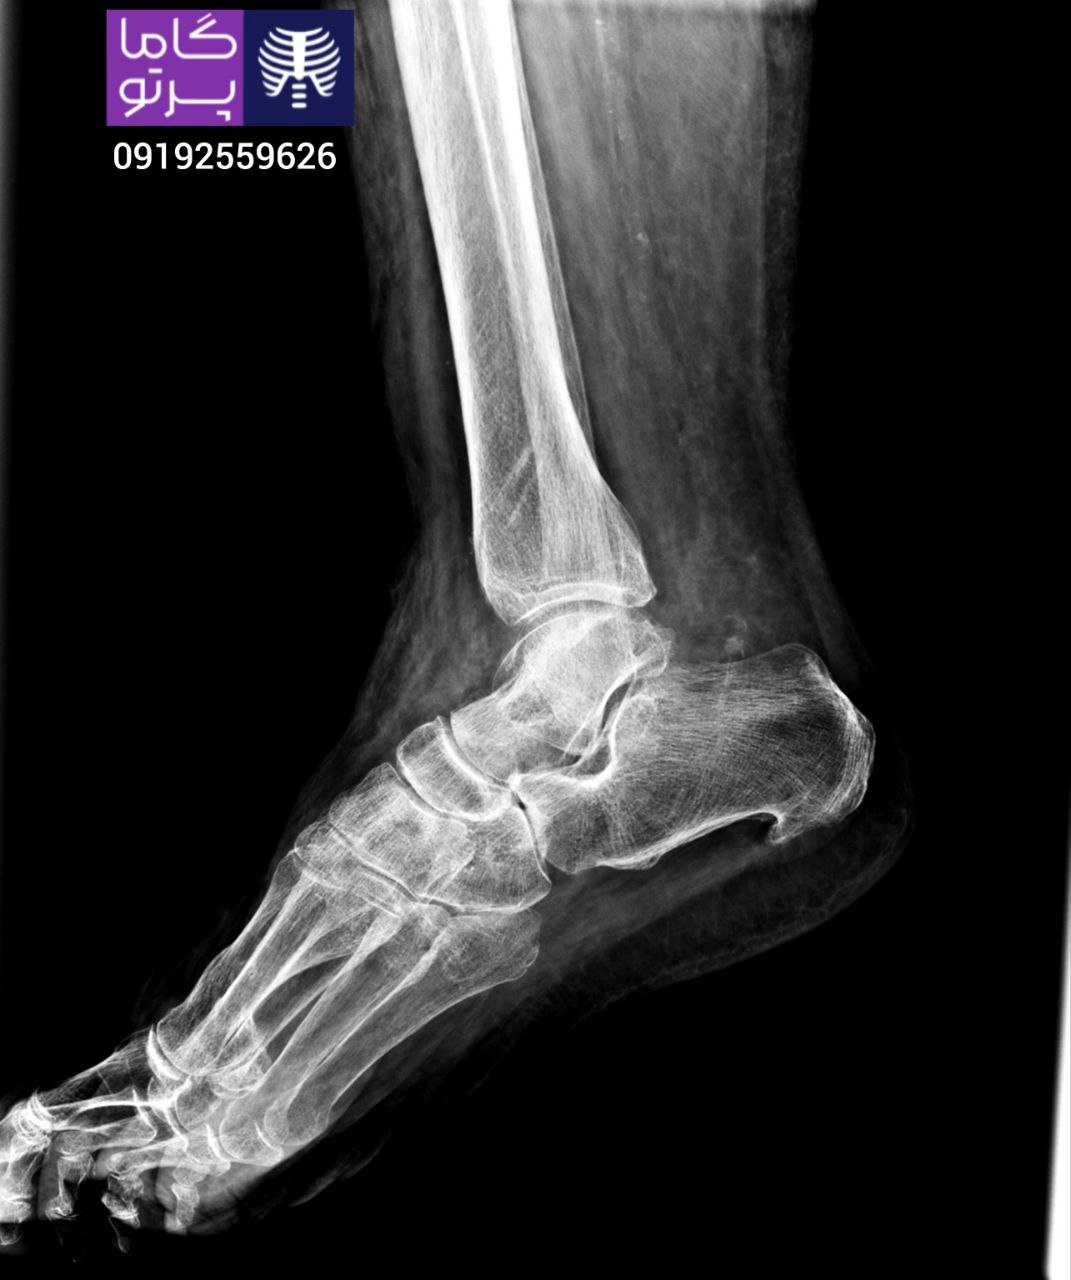

تصاویری از رادیولوژی در منزل توسط گاما پرتو

در این روش تصویر برداری یک صفحه (گیرنده یا دتکتور) در زیر عضو و قسمت مورد نظر قرار داده می شود و اشعه ایکس(دُز از اشعه جهت تشخیص) به همان قسمت که روی صفحه قرار گرفته تابنده می شود و توسط صفحه اطلاعات دریافت می شوند و همین اطلاعات پس از پردازش های لازم در نهایت عکس رادیولوژی به ما ارائه می دهد. کاربردهای رادیولوژی در منزل دقیقاً همان کاربرد رادیولوژی در بیمارستان ها می باشد از جمله بررسی انواع شکستگی ها، دررفتگی مفاصل، آرتروز مفاصل، دیدن پروتز های داخل استخوان از نظر بررسی موقعیت پروتز، آب آوردگی ریه(اِدم وافیوژن) و عفونت ریه، شکستگی دنده ها، انساد و وجود هوا در شکم و… می باشند. رادیولوژی در منزل تمام این خدمات را ارائه می دهد.